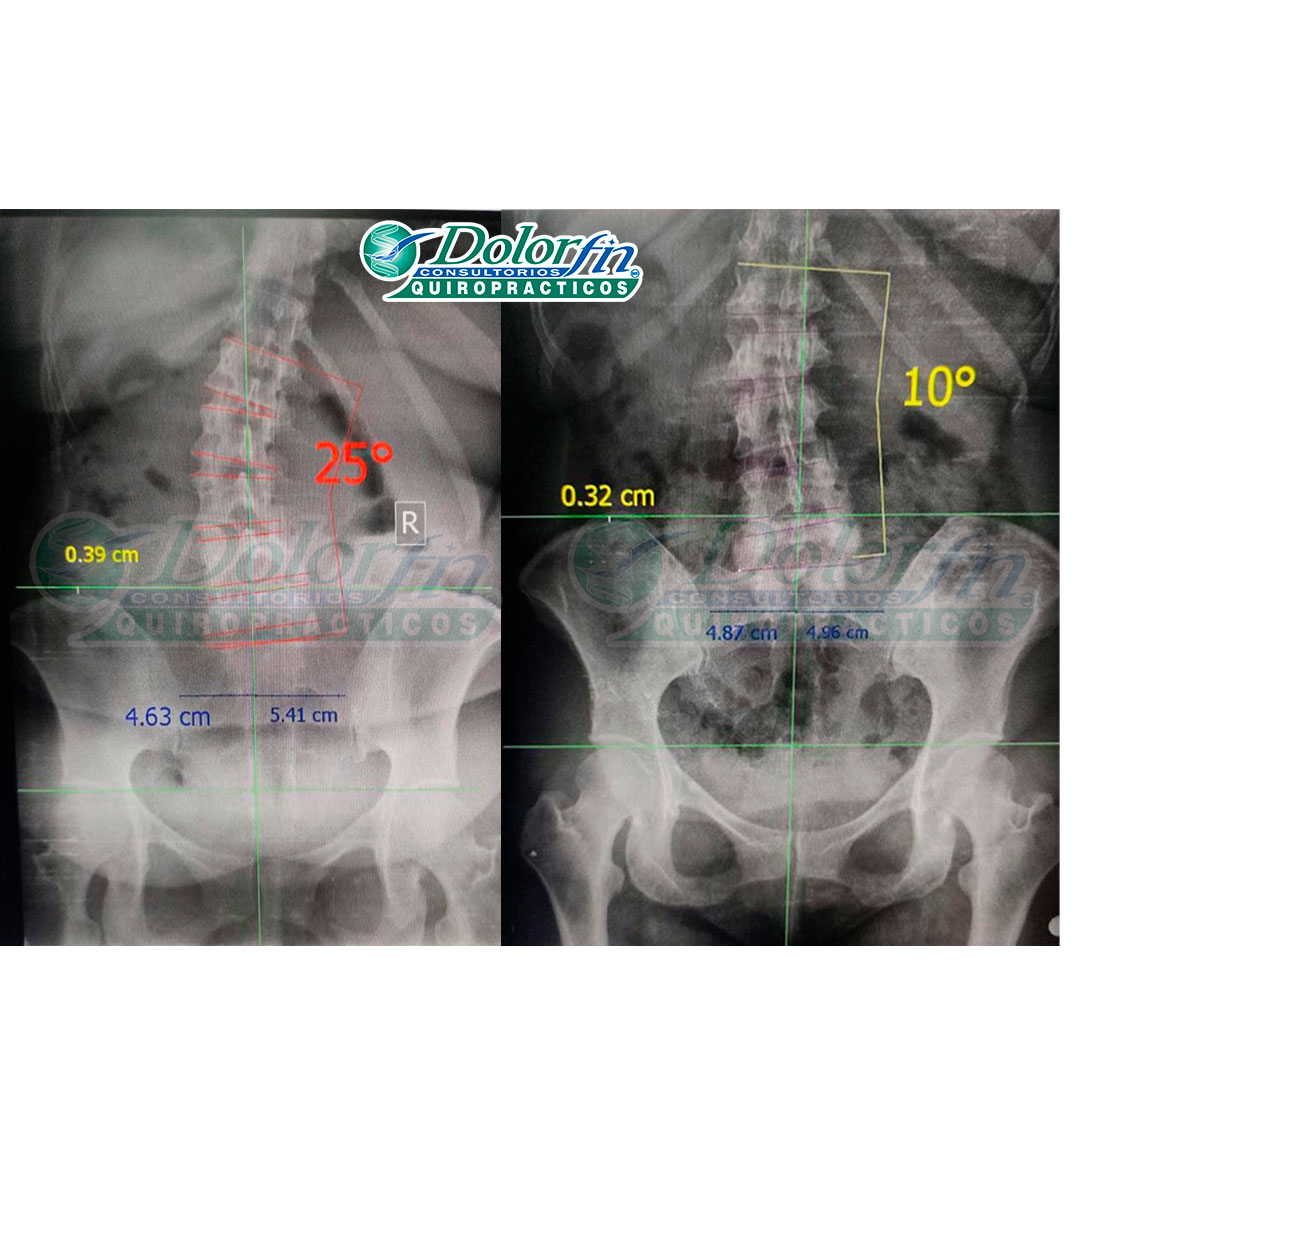

La clave del éxito radica en la constancia y en un diagnóstico preciso. Antes de iniciar cualquier tratamiento, realizamos una evaluación exhaustiva que incluye valoraciones y exámenes completos, asegurando así un plan de tratamiento personalizado y efectivo.

- Diagnósticos Precisos: Evaluaciones exhaustivas para garantizar tratamientos efectivos.